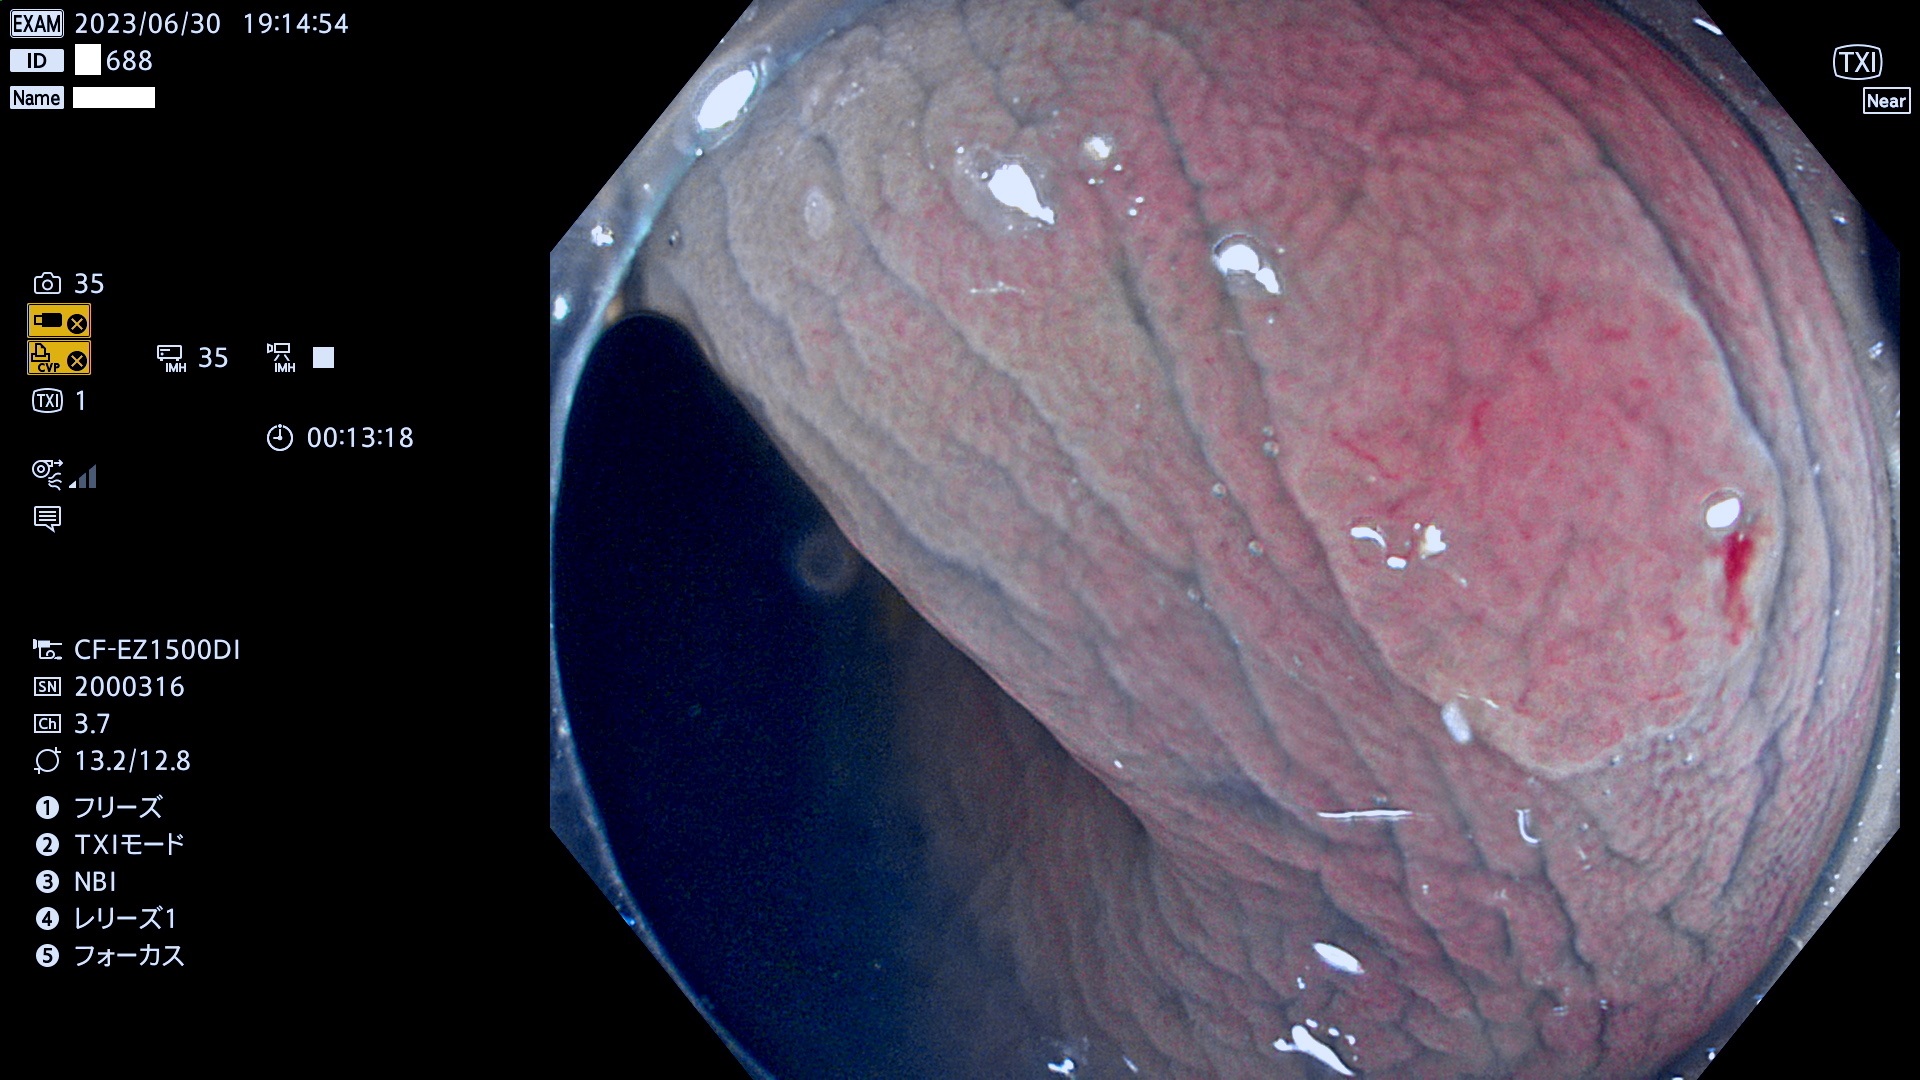

「表面型腫瘍」の中で、完全に平坦な物をUb、陥凹している物をUcと呼びます。平坦隆起型(Ua)よりも、発見が難しく危険な病変です。このタイプの発見率は「腺腫発見率」よりも、遥かに重要な意義があります。

抽出の対象期間 2023年6月29日(木)〜7月2(日)の4日間(48件の検査)8件